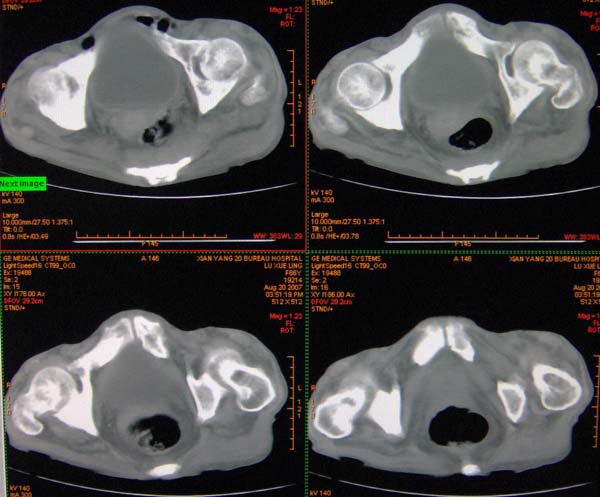

以下是引用ybing在2007-8-22 20:31:00的发言:[br]左侧髂骨溶骨样破坏;软组织肿块形成;其内未见肿瘤骨考虑纤维肉瘤或滑膜肉瘤不除外转移瘤

以下是引用qiushi在2007-8-22 21:39:00的发言:[br]双侧髂骨、骶骨侧快呈溶骨样骨质破坏,边缘模糊,左侧髂骨见骨折线,左侧髂部见软组织块影。考虑骨纤维肉瘤(中央型)伴病理性骨折,不排除骨髓瘤。建议本--周氏蛋白检查。[br] 鉴别点:[br] 骨纤维肉瘤,中央型者示边缘模糊的囊状溶骨破坏,一般无骨膜反映,可膨胀变形,突破骨皮质可形成软组织肿块,或并发病理性骨折。[br] 骨髓瘤,常表现为广泛的骨质疏松,皮质变薄或破坏,呈粟栗状、穿凿状、鼠咬状骨质破坏,边缘清晰,周围无硬化。[br] 骨转移瘤(溶骨型),表现为虫噬样、泡沫状圆形或卵圆形破坏区,很少出现软组织块影。[br][br][本贴已被 qiushi 于 2007-8-23 6:20:19 修改过]